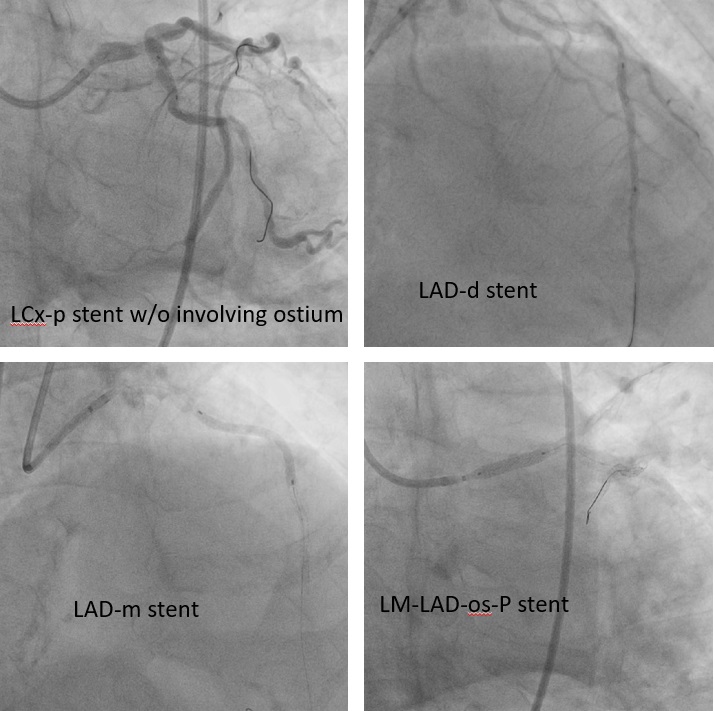

Suboptimal balloon dilation led to implantation of a 2.75 ¡¿ 8 mm Onyx DES at the LCX ostium. The LAD was predilated and treated with 2.0 ¡¿ 38 mm and 2.5 ¡¿ 38 mm Xience Sierra stents plus a 3.5 ¡¿ 15 mm Megatron for LM–LAD. IVUS confirmed full stent expansion and apposition with no residual stenosis. A minor LAD ostial type II dissection was observed but without flow limitation.